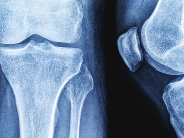

퇴행성 관절염 초기증상과 관리법 – 무릎에서 시작되는 관절의 SOS

1. 퇴행성 관절염이란?

| 정의 | 관절 연골이 닳고 손상되며, 뼈와 뼈 사이 마찰로 염증과 통증이 생기는 질환 |

| 발생 부위 | 무릎, 고관절, 손가락, 척추 등 |

| 특징 | 만성적이고 점진적으로 진행되며, 50대 이상 여성에게 흔함 |

| 주요 원인 | 노화, 과체중, 반복적인 관절 사용, 외상, 유전 등 |